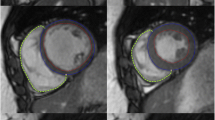

The semi-automatic segmentation method (QMass MR research edition, Medis, Leiden, The Netherlands) was based on the signal intensity distribution of MR images. The technique of normalized convolution [18] is used to estimate the spatially varying blood and muscle intensities within a user-provided epicardial contour. The voxel intensity is defined by a first order model with six variables:

where a0, a1, a2, b0, b1 and b2 are constants that vary among scans according to the grey value distribution of the image within the epicardial contour. I m(x, y) and I b(x, y) represent the approximation of the intensity of muscle and blood, respectively, at the position (x, y) (see Fig. 4). The constants are obtained with an iterative optimization procedure, during which the weight w(x, y) is initialized to either 1 or 0 using the Otsu threshold method [19].The procedure is stopped when the classification w > 0.5 is unaltered between iterations or when the number of iterations exceeds ten.

Segmentation procedure. a Shows a short axis view of the heart. The signal intensities along the red line in a are represented in b. The algorithm fits two planes (represented by the solid black lines) through the highest (blood) and lowest (muscle) signal intensities within the epicardium. A threshold plane was defined at 70 % between the two intensity planes. Voxels with signal intensities above this threshold are considered pure blood, and voxels with signal intensities below this threshold are considered to be pure muscle

A binary classification is obtained by thresholding w(x, y). If w(x, y) is higher than the threshold value, the voxel is considered pure blood, otherwise it is defined as pure muscle. In this experiment the threshold value was set to 70 %. Blood volume measures are obtained by multiplying the number of voxels classified as blood with the voxel volume.